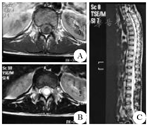

Axial and sagittal MR imaging of the schwannoma

A:轴位T1WI,肿瘤呈稍低信号,边界尚清;B、C:矢状位、轴位T2WI,肿瘤呈高信号,边界清楚,且可见脊髓空洞

MRI是诊断椎管内占位病变的有效手段,因而不难区分髓内和髓外肿瘤,但髓内神经鞘瘤却没有特异性征象。目前,有关髓内神经鞘瘤影像学表现的报道较少,而且部分病例的MRI资料不全,多数学者认为髓内神经鞘瘤具有髓外硬膜内神经鞘瘤相似的影像学表现。一般来说,髓内神经鞘瘤MRI表现为T1WI等或稍低信号,T2WI等或稍高信号,多与脊髓界限清晰,可伴有脊髓空洞、水肿或囊变,注药增强扫描后可见肿瘤实质明显均匀强化且边界清晰[10]。本例肿瘤实质为稍低T1、高T2信号,其内可见明显的囊变区,增强后肿瘤实质部分强化明显均匀,边界清楚,且继发有脊髓空洞,这些表现虽与神经鞘瘤的典型征象相一致,但由于髓内神经鞘瘤发病率极低,故容易导致误诊。因此,结合此次诊疗经验,当MRI检查显示髓内病变显著强化、边界光滑清晰时应想到神经鞘瘤的可能。钱银峰等[11]总结以下征象有助于神经鞘瘤的诊断:(1)肿块以等或稍长T1、等或长T2信号为主,常伴有囊变;(2)增强后实质部分明显强化,且强化较均匀;(3)增强后肿瘤边界消楚;(4)肿瘤多较小,常不超过3个椎体节段;(5)肿瘤相连髓外神经根增粗(具有特征性,但较少见)。Kim等[12]认为瘤周水肿轻微是其特征之一。本组瘤周水肿较轻微,符合其特征性表现,但本组患者肿瘤较大,跨位T9~L1,提示肿瘤大小无明显诊断特异性。